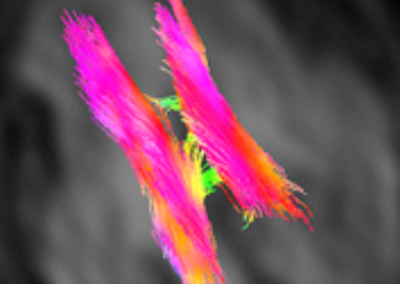

L’Université Paris Cité franchit une nouvelle étape dans le domaine de l’imagerie médicale anténatale avec l’acquisition d’un système d’Imagerie par Résonance Magnétique (IRM) 1,5T ARTIST™ de GE HealthCare. Cet équipement de pointe renforce les capacités de la Plateforme LUMIERE à l’hôpital Necker-Enfants malades, plateforme intégrée de soins, de recherche clinique et d’enseignement en imagerie médicale de la femme enceinte, du fœtus et du placenta.

L’acquisition de cette nouvelle IRM s’inscrit dans le cadre du protocole de recherche « LUMIERE SUR LE FETUS », dont les objectifs sont d’améliorer la prise en charge des pathologies anténatales, d’affiner leur pronostic et de contribuer à la réduction de la morbidité et de la mortalité à court, moyen et long terme. Cette acquisition a été rendue possible grâce au don exceptionnel de la Fondation LUMIERE d’un montant de 250k euros ainsi qu’au soutien de l’Université Paris Cité à hauteur de 670k euros.

L’inclusion de ces patientes, depuis leur accueil jusqu’à la réalisation des examens d’imagerie, puis l’analyse des images et l’interprétation des résultats par des équipes expertes, enrichit une base de données structurée, unique au monde, au service de la recherche et de l’innovation en imagerie anténatale et en médecine fœtale.

La Plateforme LUMIERE accueille chaque année plusieurs jeunes chercheurs (masters, doctorants et post-doctorants). Leurs travaux de recherche visent, à terme, à améliorer le diagnostic et le pronostic des pathologies anténatales, afin de mieux anticiper et optimiser la prise en charge des nouveau-nés. Ces travaux ont déjà mené à des communications et des publications scientifiques dans des revues à comité de lecture.

En soutenant des vocations scientifiques et en accompagnant celles et ceux qui construisent la recherche de demain, la Plateforme LUMIERE contribue activement à l’enrichissement des connaissances sur le développement fœtal et placentaire.